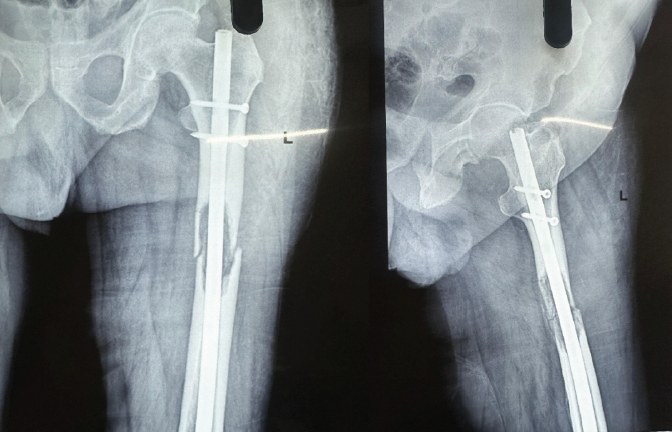

Plain radiographs of the pelvis and femur (anteroposterior and lateral views) demonstrated a subtrochanteric, lytic lesion confined within the cortex of the left femur (Fig. 1). The contralateral femur appeared normal. Magnetic resonance imaging confirmed a pathological subtrochanteric fracture secondary to lymphoma (Fig. 2).

Figure 1 : Anteroposterior (AP) and lateral radiographs of the pelvis and left femur demonstrating a subtrochanteric lytic lesion confined within the cortex of the left femur (70-year-old male with large B-cell lymphoma). The subtrochanteric location and lytic appearance are characteristic of pathological fracture secondary to lymphoma.

Figure 2 : Postoperative anteroposterior (AP) and lateral radiographs of the left femur following intramedullary nailing with long femoral nail and proximal interlocking screws. The radiographs demonstrate acceptable fracture reduction and proper implant positioning. The locked intramedullary nail provides rigid fixation spanning the pathological lesion, allowing early weight-bearing and mobilization.